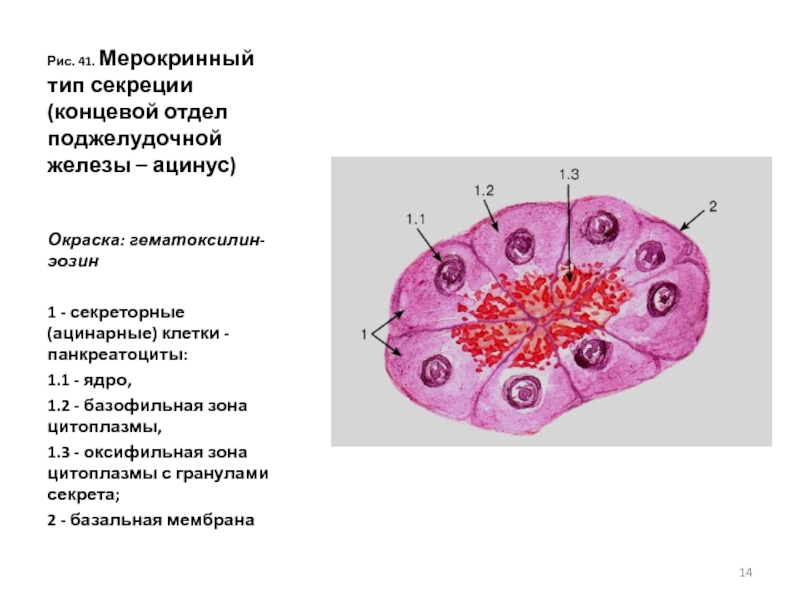

Структура клеток: Эктоплазма и цитоплазма в научных изображениях